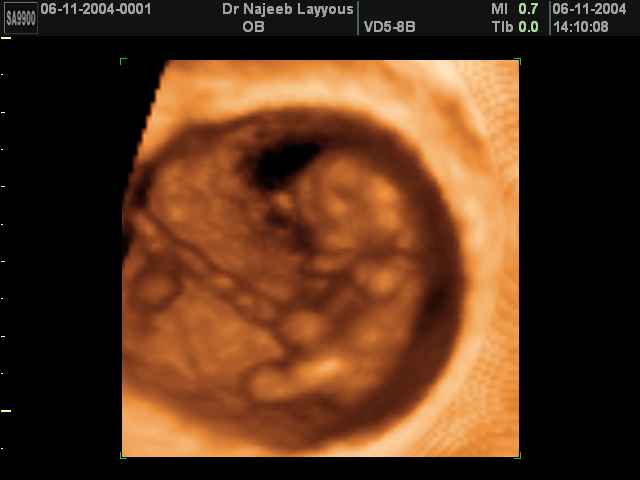

- First Trimester Ultrasound Photos

3D First Trimester Ultrasound Scan Photos ( Early Pregnancy Ultrasound Photos ) | Dr N Layyous